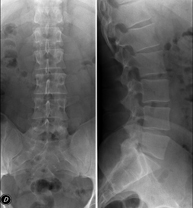

- RX Columna lumbar

Técnica mediante la cual, utilizando rayos X, se obtienen imágenes de la columna lumbar para su estudio.

Técnica mediante la cual, utilizando rayos X, se obtienen imágenes de la columna lumbar para su estudio. Indicaciones: ciática, traumatismo, dolor lumbar.